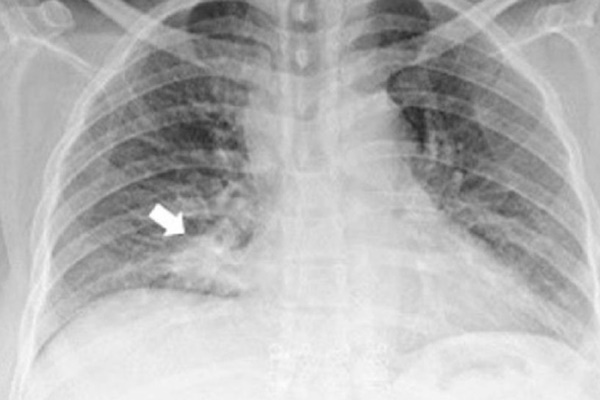

Cuối cùng, kết quả chụp X-quang ngực và quét toàn bộ cơ thể đã tiết lộ thủ phạm - một khối mô ung thư đang phát triển ở phần dưới phổi phải của người phụ nữ. Khối u này đã lan đến nhiều cơ quan khác, bao gồm cả phần mắt được gọi là màng đệm.